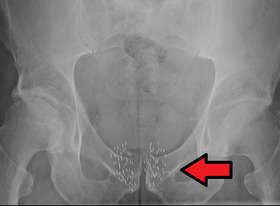

Brachytherapybeads.png

Arrow points to brachytherapy beads used to treat prostate cancer.